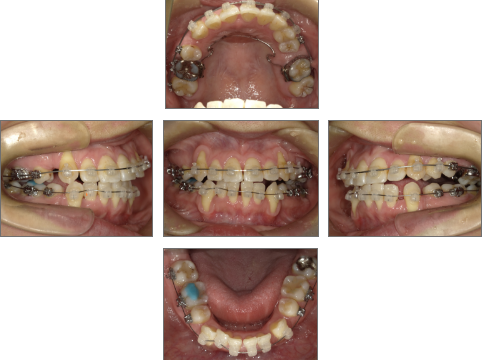

【治療経過】

●治療に用いた主な装置

セラミックブラケット

●メンテナンス頻度

月1回